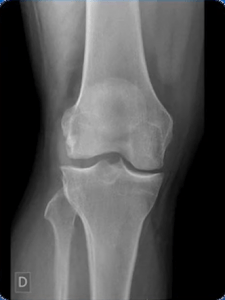

O contraste radiográfico pode ser definido como a diferença entre as densidades das estruturas registradas em um filme radiográfico, máximo (preto) e mínimo (branco) da imagem radiográfica, podendo ser influenciado pelo nível de exposição e pela radiação espalhada. Quanto maior a diferença das densidades maior é o contraste obtido em uma imagem radiográfica.

O fator de qualidade para controlar primariamente o contraste é o KV, também chamado de KVP ou DDP (diferença de potencial) que define um feixe de maior ou menor qualidade, quanto maior a qualidade mais energético é o feixe, e quanto menor a qualidade menos energético. Quando o KV tem uma alta qualidade obtém um grande poder de penetração sendo assim chamado de raios duros, o mesmo vale para quando se tem uma baixa qualidade sendo chamado de raios moles.

Alto contraste

- Pouco tons de cinza

- Visto com facilidade o que é negro e o que é branco

Baixo contraste

- Difícil visualização do que é negro e o que é branco

- Muitos tons de cinza

- Alta kilovoltagem = Baixo contraste visual e grande escala de contraste

- Baixa kilovoltagem = Alto contraste visual e curta escala de contraste